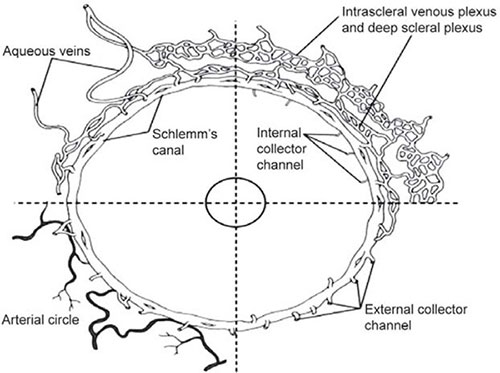

The 25 to 35 collector channels drain the canal of Schlemm at irregular intervals into three interconnecting venous plexuses: the deep, mid and episcleral venous plexuses (Figure 1.6). The aqueous veins drain directly onto the episcleral plexus.24 There are no valves in the system.

FIGURE 1.6: Schematic representation of aqueous humor outflow distal or beyond the conventional or trabecular pathway and into the canal of Schlemm. The internal collector channels of Sondermann are labeled in the upper right sector as they extend into the trabecular meshwork. The external collector channels are seen in the upper and lower right sectors, arising from the canal and uniting with the deep intrascleral plexus extending directly to the episcleral veins. The deep and intrascleral venous plexuses are external to the canal. In the upper left sector an aqueous vein arises from the deep scleral plexus and another arises from Schlemm's canal and runs directly to the episcleral venous plexus. External collector veins are seen to arise from the canal and join the deep scleral plexus. In the lower left sector, the arteries of the deep sclera are seen to be in close relation to the canal of Schlemm.(From Hogan MA, Alvarado J, Weddell J. Histology of the human eye. Philadelphia: WB Saunders, 1971)